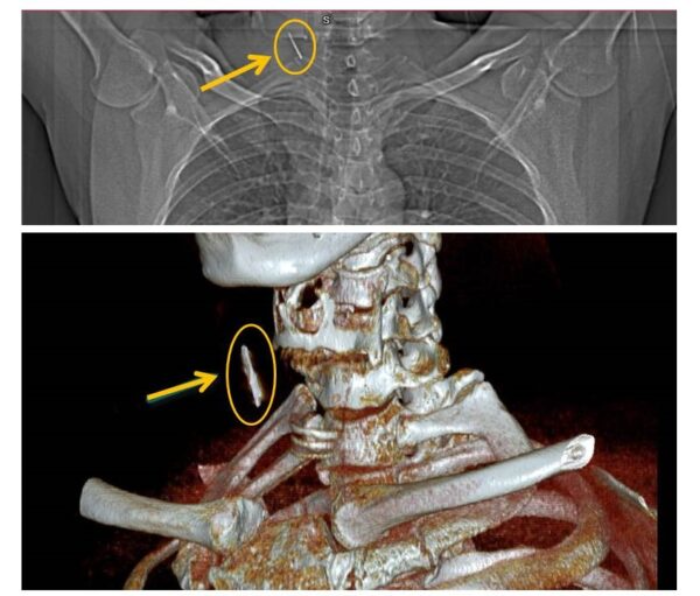

On June 24, surgeons successfully removed the rusty nail, which was surrounded by fibrous tissue and measured about 2.5 cm. The patient’s condition was stable post-surgery, and he was expected to be discharged within a few days.

In this case, the nail was located between the sternocleidomastoid muscle and the shoulder-hyoid muscle, avoiding major blood vessels and thus not posing an immediate threat.